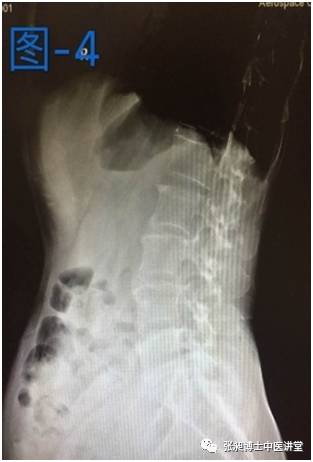

后来这位患者经过两个月的小针刀治疗后疼痛缓解,右侧强迫体位缓解,生活质量也得到很大提高。腰椎侧弯也好转,如下图所示,是患者治疗前和治疗后的对比。